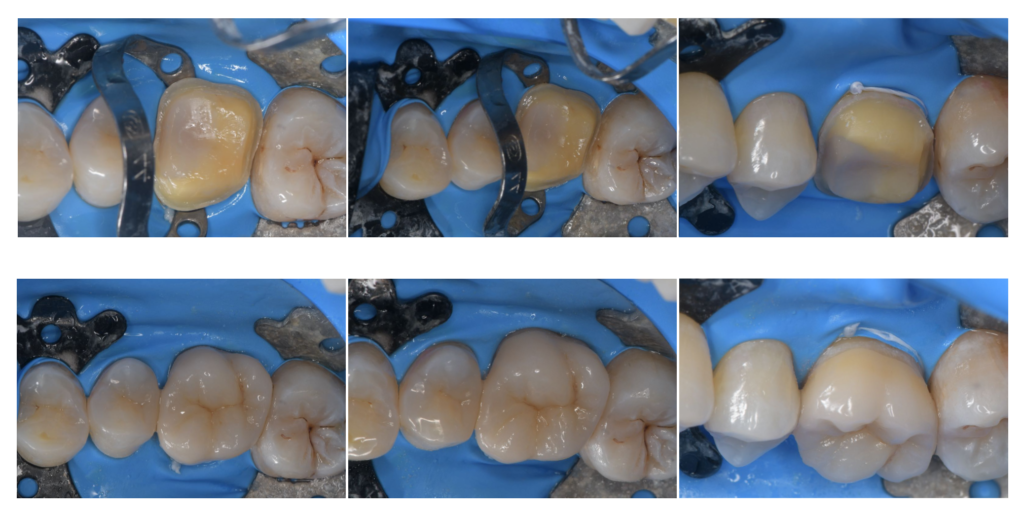

MI

虫歯治療では、正確に虫歯を除去し、菌がいない状態を目指すことが求められます。

詳しく見る